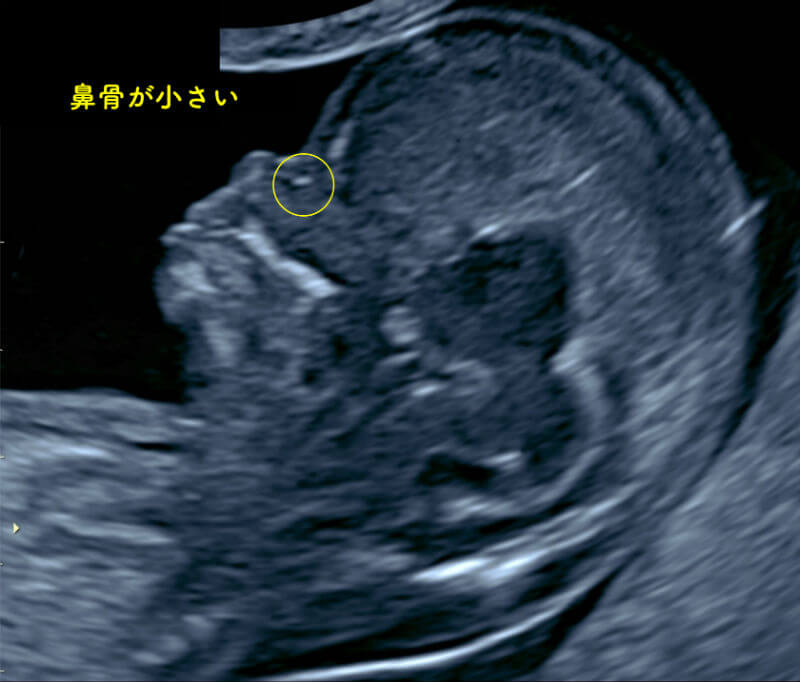

エコー写真わかる ダウン症の特徴 むくみ等 出生前診断のこころえ

エコー写真わかる ダウン症の特徴 むくみ等 出生前診断のこころえ

ダウン症エコー写真 週目によるbpd Nt Flを解説 ダウン症ステーション

エコー写真わかる ダウン症の特徴 むくみ等 出生前診断のこころえ

ダウン症のエコー特徴 手足 頭 Bpd Nt Fl徹底解説 Down And Up